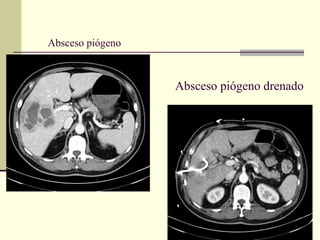

Absceso piógeno

Absceso piógeno drenado

Absceso hepático - Diagnóstico

2.2 Tomografía (TC): tiene una sensibilidad de 95 – 100%. Con

contraste permite detectar lesiones de 0.5 – 1cm.